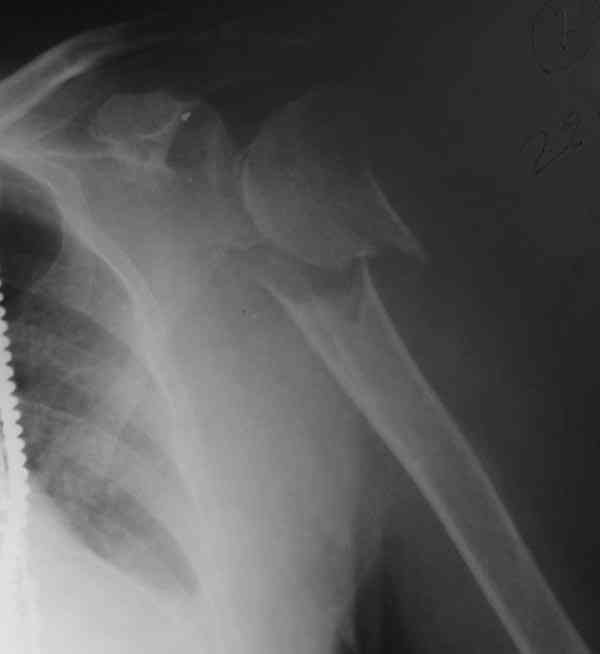

I am attaching the radiographs of the mother of a doctor. She has chronic renal failure for >10 years, diabetes mellitus and coronary artery disease. Age 62. She was offered the options of non-surgical management in a sling and surgery with a locking plate. She was given Tramadol for pain relief. Five days after injury, patient requested surgery, because of pain, inability to move without pain.

The reduction is not perfect. The patient is very small made, and it was difficult to bring the plate proximally without impingement in abduction.

Pain relief after surgery was early and sustained.